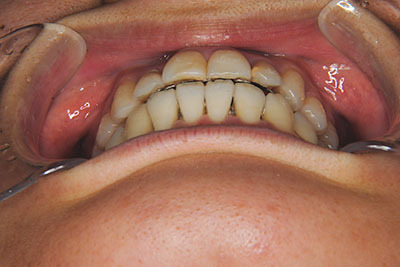

おとなの方でも矯正治療をあきらめないでください!

矯正歯科治療は子供の頃だけしかできない……

子供の頃に比べ大人になったら治療期間がすごく長い……

というようなイメージをお持ちではありませんか?

子供の頃に矯正治療を行う方が治療期間が短く済むというのは、確かですが、矯正治療は患者様の意識も重要です。

いくら歯が動き易くとも、本人がやる気でなければ効果は出ませんし、むし歯発生のリスクも高まります。おとなの方は顎の成長が終わっているため、治療の計画が立てやすいとも言えます。「もう大人だから…」とあきらめず、一度ご相談ください。